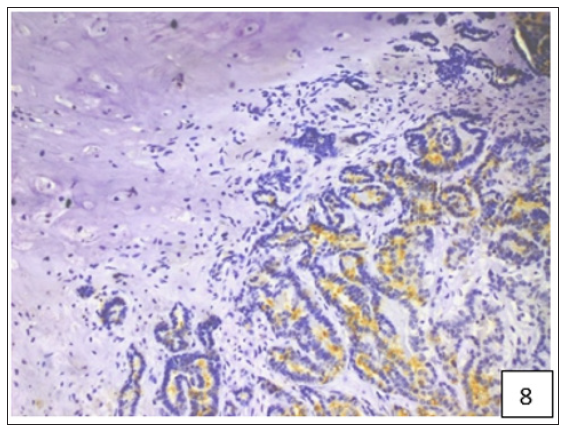

The average staining index of BCRP was 6.9, 7.75 and 7.92 in grade 1, 2 and 3 tumours, respectively (Figure 4). High expression of BCRP was observed in undifferentiated as compared to the well differentiated CMT cases. The average staining index of BCRP immunoreactivity in the cases of mammary sarcoma, carcinoma and carcinosarcoma in the present study was 6.28, 7.57, and 8.2, respectively (Figure 5). Variable cytoplasmic and membranous immunoreactivity of MDR1 was observed in the epithelial cells, immature connective tissue and EMT in all the 53 cases of CMT (Figures 6-7). A weak MDR1 reactivity in immature connective tissue was noted in comparison to its no reactivity in mature connective tissue (Figure 8). In addition, blood vessel endothelium, ductular epithelium and tumour emboli showed positive immunoreactivity for MDR1. On the basis of staining intensity, 18 cases revealed weak (+), 24 cases moderate (++) and 11 cases strong (+++) immunoreaction.

Figure 8:A weak MDR1 reactivity in immature connective tissue was noted in comparison to its no reactivity in mature connective tissue.